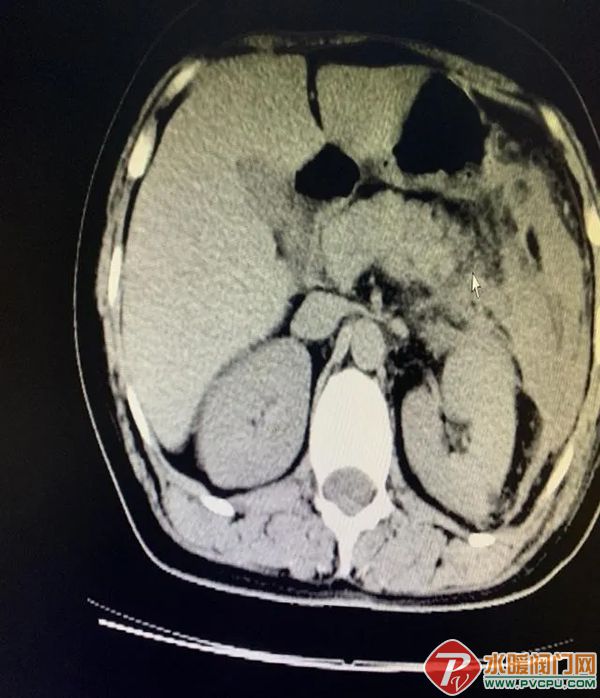

近日,患者洪某某,因持续腹痛5天,在外院初步诊断为肠梗阻,为求进一步治疗转诊至仑苍镇卫生院。 接诊后,仑苍镇卫生院医生高度重视,迅速为患者展开细致检查。当抽血结果显示血淀粉酶显著升高,结合腹部CT影像学表现,医务人员凭借扎实的临床经验,敏锐地鉴别:并非单纯性肠梗阻,而是急性胰腺炎继发的麻痹性肠梗阻! 急性胰腺炎起病急、进展快、病情凶险,早期精准识别是救治关键。此次及时鉴别为后续规范救治争取了宝贵时间。 为确保患者得到专业救治,仑苍镇卫生院迅速启动救治流程,第一时间对接南安市医院消化内科庄宇亮副主任医师。在庄主任的悉心指导下,仑苍镇卫生院医护团队快速为患者制定个体化综合治疗方案,及时开展胃肠减压、导泻、抑酶、补液等规范治疗,全程密切监测患者生命体征,根据病情变化及时调整诊疗方案,全力保障救治效果。 经庄主任及仑苍镇卫生院医护人员精心诊疗、细致护理,患者病情得到快速控制,腹痛症状显著缓解,生命体征平稳,各项指标逐步恢复正常。经数日规范治疗,患者痊愈出院。 出院那一刻,她紧紧握住医护人员的手,由衷感谢:“没想到在卫生院也能得到这么专业的治疗,有你们在,我心里踏实多了。”朴实的话语,道出了最真挚的感动。 此次急性胰腺炎患者的成功救治,正是仑苍镇卫生院践行医者使命、守护群众健康的真实写照。一直以来,仑苍镇卫生院始终坚持“以患者为中心”,不断加强学科建设,提升诊疗技术水平,持续强化急危重症救治能力。我们深知,每一次能力的提升,努力让群众在家门口就能享受到安全、优质的医疗服务。 未来,仑苍镇卫生院将继续坚守医者初心,以更精湛的技术、更温暖的服务,全力守护全镇人民的生命健康,做百姓信得过、靠得住的健康守门人!